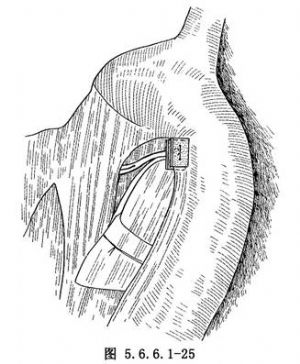

如肿瘤位置较高不能作弓下吻合,应作主动脉弓上吻合,需要将食管继续向上游离。在主动脉弓下缘常有1~2支直接来源于主动脉的食管固有动脉供应食管,要仔细分出,用丝线结扎后切断,不能贸然剪断,否则将造成危险的大出血(图5.6.6.1-21)。一旦固有动脉被损伤,切记不可用止血钳乱夹,术者可用右手示指尖按压出血处(图5.6.6.1-22)。然后用无损伤针及2/0号涤纶线携带一个1cm×1.5cm大的涤纶补片,由按压出血处的示指端右缘进针,由指端左缘出针,用缝线另一端的针由距离前一针0.6cm处的下方再缝一针(图5.6.6.1-23)。两根针再次穿过另一块补片(图5.6.6.1-24)。抽出按压出血处的手指,结扎涤纶线(图5.6.6.1-25)。每个缝线打结6次,如仍有小渗血可补缝数针。正确处理食管在主动脉弓下的固有动脉的方法为由主动脉弓下缘仔细解剖,找出血管后结扎,或切开主动脉弓上缘的纵隔胸膜,用手指由主动脉弓后方、食管前壁与主动脉弓之间轻轻向下外方向顶,即可将固有动脉由弓下显露。如固有动脉位置较深,可用手指尖端由主动脉下方,食管前壁与主动脉弓之间轻轻向上顶,即可将固有动脉由弓上显露(图5.6.6.1-26)。将固有动脉处理完后,即可将已在贲门处切断的食管由主动脉后方提至弓前方作吻合(图5.6.6.1-27)。